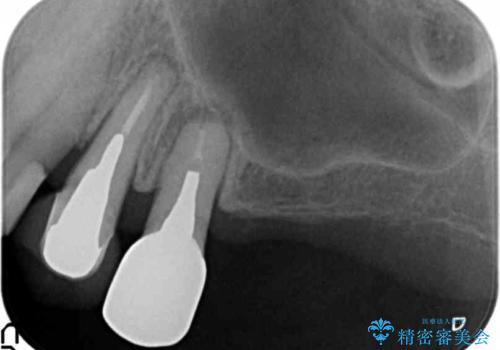

- 根管治療の後、部分矯正にて歯軸と歯茎のラインを整えます。

最終的に、前歯2本にて大きさの調整を行い完成させます。

根管治療は顕微鏡を用いて丁寧にやり直し、今後問題が起きてこないよう予防します。

部分矯正により無事歯ぐきのラインもそろい、最終的には前歯2本で色や形態を揃えて製作することになりました。